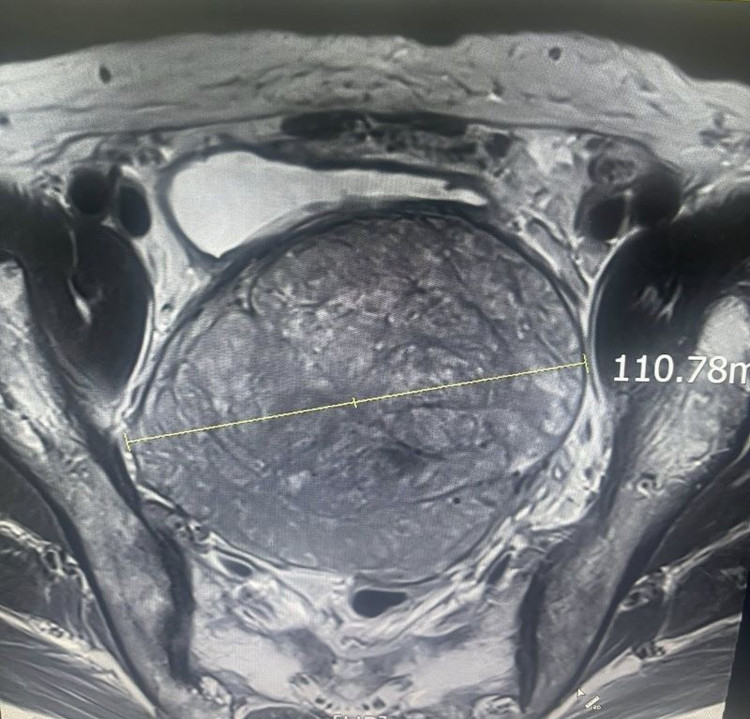

tien-liet-3.jpg

Khối u có kích thước khổng lồ trên phim chụp - Ảnh BVCC

tien-liet1.jpg

Kích thước khối u khổng lồ trên phim chụp - Ảnh BVCC